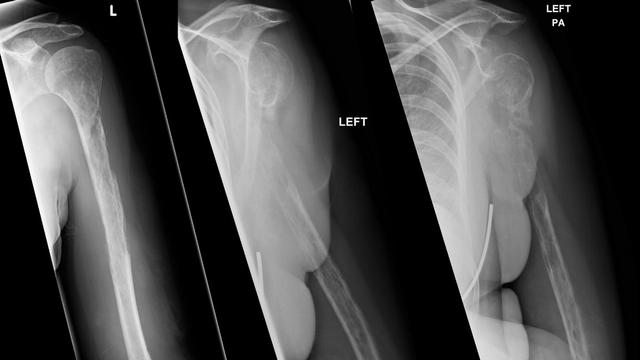

Derita Penyakit Langka Tulang Lengan Wanita Ini Tiba Tiba Hilang Global Liputan6 Com